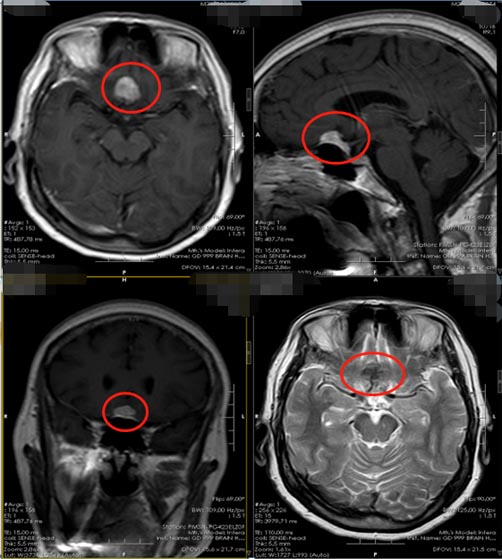

但一个多月来,头痛老是反反复复,家人觉得蹊跷:感冒也不至于这么长时间啊?当地医院就诊,头颅核磁共振检查还真发现了问题:“前颅窝底占位性病变,考虑脑膜瘤可能”。

颅底脑膜瘤需要手术治疗,手术切除是唯一能够将脑膜瘤完全去除的方法。颅底脑膜瘤手术难度比较高,因为肿瘤的位置比较深,并且与周围神经和血管可以出现粘连;手术原则是在保全重要的神经血管和脑组织的前提下,全切除肿瘤;因此根据肿瘤的大小、位置以及蔓延的方向,选用最佳的手术入路,同时结合现代颅底显微手术技术,切除肿瘤、减少脑组织损伤是提高手术疗效的关键。

医院副院长、神经外五科主任鲁明在充分了解患者的病情后,决定选择微创:经右侧眉弓入路行前颅窝底脑膜瘤切除术。微创手术是利用锁孔一样大小的骨窗来代替过去大切口、大骨窗,进行颅内的病变切除,具有对患者心理影响小、开关颅时间短、对脑组织牵拉小、减少了无效开颅等优势,以更小的切口、更少的出血、更少的神经功能损伤、更快的术后恢复,使患者获得最大的收益。